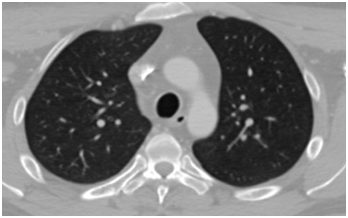

No discarded tumor activity suggested in lung nodule surveillance (Figure 3). Surgical resection of primary lesion dimensional oncologic margins and partial thickness graft of skin. Cervical treatment was delayed until recovery program (Figure 4) (Figure 5); HPR: high-grade mucoepidermoid carcinoma with vascular lymphatic permeation and extensive areas of necrosis and perineural invasion. Tumor size: 14x10x9cm-free surgical margins of neoplasia; the closest to 2cm, 2.6cm surgical bed to the IHC neoplasia: PAS with and without diastase alcian blue and mucicarmine: Positive for mucin (+++), cytokeratin 7, cytokeratin 8 p.63. Epithelial Membrane antigen: Positive focal (++), cytokeratin 14, cytokeratin 20. TTF -1: Negative (-) (Figure 6) (Figure 7).

Figure 4 CT Scan. Right pulmonary apical mass, suspicious for metastatic disease <6mm.